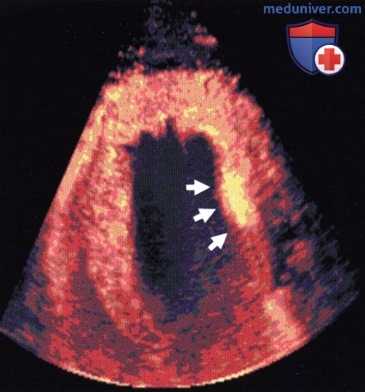

Маркировка статичных лейкоцитов в сердце свиньи через 20 мин после инъекции. Контрастное средство обнаруживается только в миокарде (стрелки: очаг постишемического воспаления).

Применение режима второй гармоники для улучшения визуализации эндокарда во время стресс-ЭхоКГ. Применение эхоконтрастного средства во время стресс-ЭхоКГ для улучшения визуализации эндокарда.